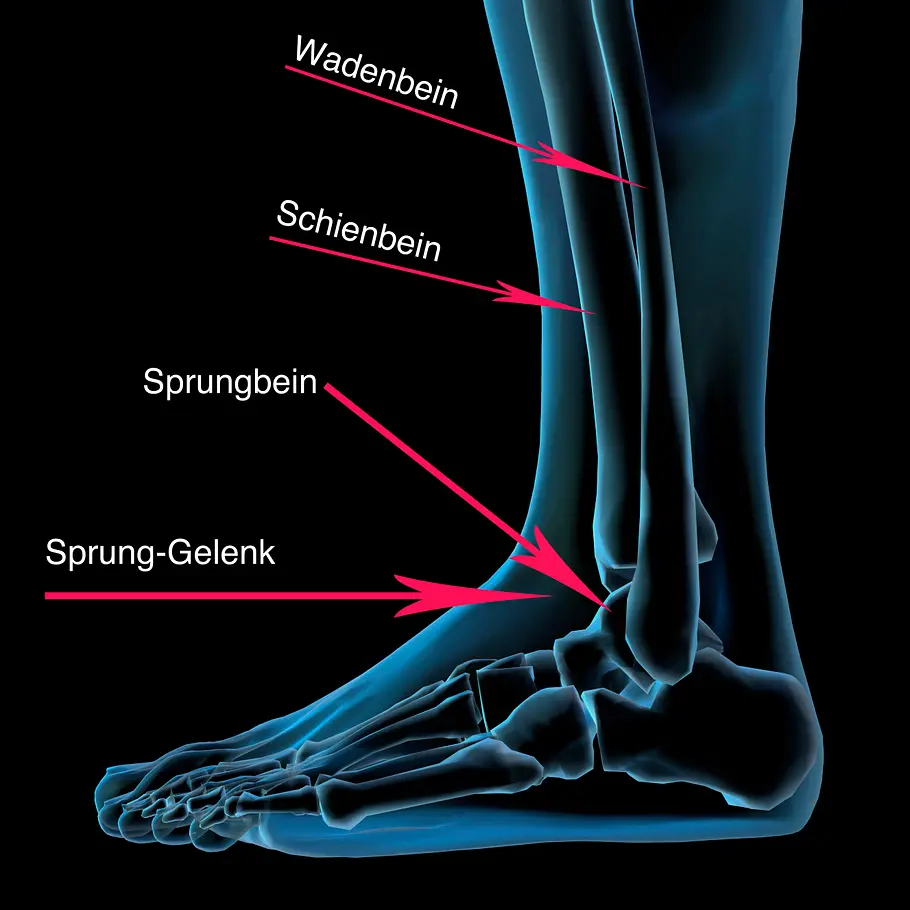

Das Sprunggelenk dient als Verbindung zwischen Fuß und Waden- und Schienbein. Wie jeder Gelenk-Knochen ist auch der Sprunggelenk-Knochen von Knorpeln umgeben. Knorpel bestehen aus einer festen, aber elastischen Masse, die den Gelenk-Knochen umhüllen und schützen.